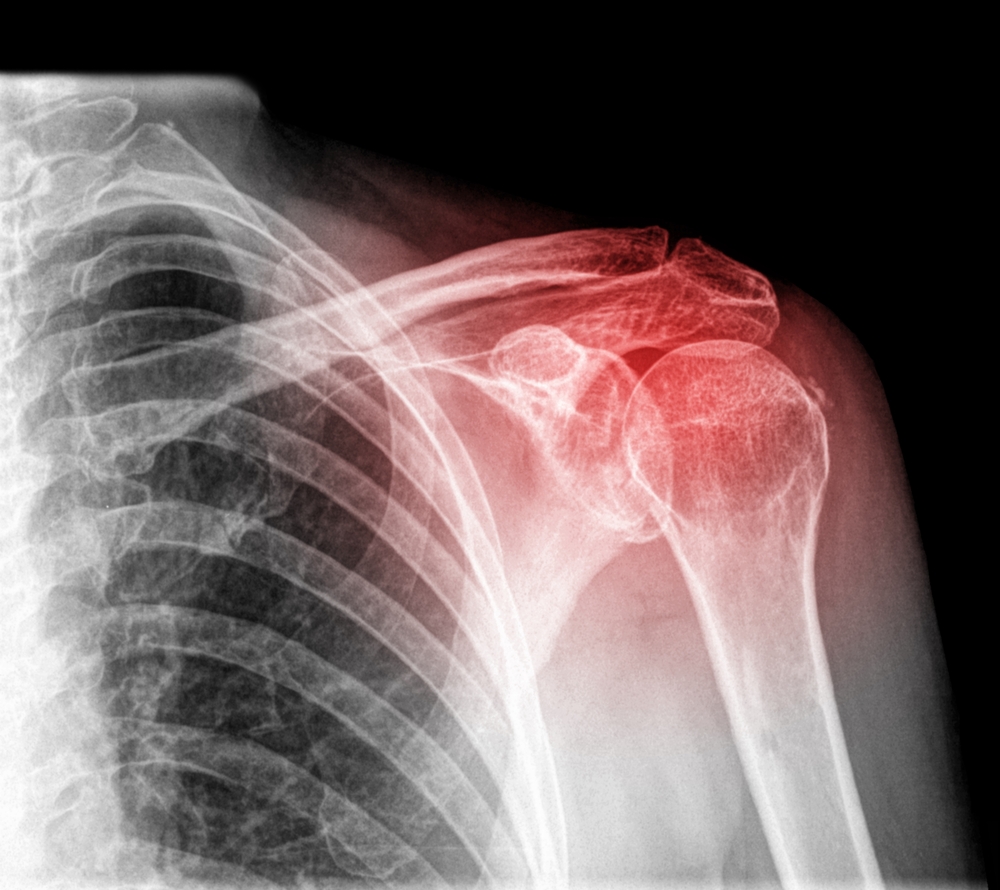

Se recomienda la operación de hombro en los siguientes casos:

osteoartritis

resultado deficiente de una cirugía anterior

artritis reumatoidea

fractura grave en el brazo cerca del hombro

tejidos muy dañados o desgarrados en el hombro

tumor en el hombro o a su alrededor.

El hombro es una enartrosis lo cual quiere decir que el extremo redondo del hueso del brazo encaja dentro de la abertura en el extremo del omóplato. Este tipo de articulación permite mover el brazo en la mayoría de las direcciones.